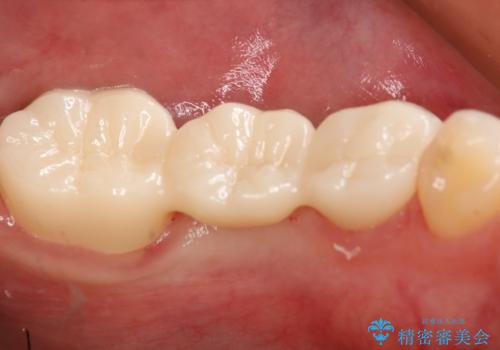

患者様の希望によりフルジルコニアブリッジを選択しました。

- 297000円(フルジルコニアクラウン×3、仮歯×3)費用は治療当時の料金となります

後ろの歯が前に倒れ込んでいましたが問題なく治療を終えることが出来ました。